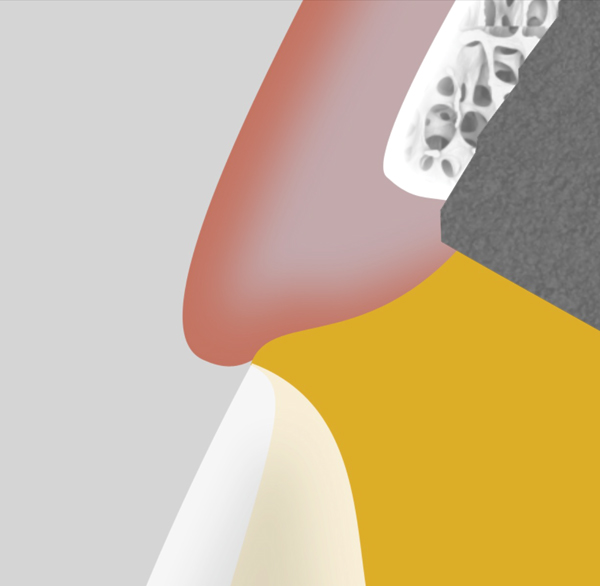

The emergence profile is the portion of the abutment from the head of the implant to the free gingival margin, and it has significant impact on the shape and position of the soft tissue. Generally, a larger diameter emergence profile will compress the soft tissue and move it apically (Figure 5), while a narrowed emergence profile will allow the soft tissue to drape in a more coronal position (Figure 6). Neither design is indicated for all situations, and the design must be based on the needs of the particular clinical scenario.

Fig 5. The “over-contoured” abutment design will displace the soft tissue apically. This design can be used strategically to reposition the peri-implant tissue to its desired position.

Figure 5

Fig 6. Useful in conjunction with immediate load scenarios, the “under-contoured” abutment design allows space for a potential increase in soft-tissue volume or a draping of tissue coronally. This design is created in the provisional restoration and left in position for at least 4 months.

Figure 6